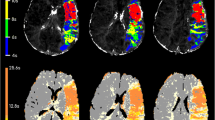

The Bland-Altman description of the data and algorithm versus algorithm correlation coefficients confirmed that the AIF/SVD and the first moment algorithms generated markedly different lesion volumes than the area/peak and TTP algorithms, with the discrepancies decreasing with increasing MTT thresholds. For pMRI maps using AIF/SVD or first moment methods with a 0-s threshold, the mean difference of the means (Bland-Altman) was only 3.35 ml whereas the differences between AIF/SVD or first moment versus TTP or area/peak varied between 52.45 ml and 67.71 ml. Concomitantly, the TTP and area/peak algorithms yielded highly correlated (all r>0.89, all P≤0.0001) but, according to the Bland-Altman description, differing volumes (all mean differences >11.91 ml), illustrating that these two algorithms both render substantially larger lesion volumes than the AIF/SVD and first moment methods. As one could expect, with increasing delays, the lesion volumes decreased for all algorithms and so did their mean differences (Bland-Altman) leading to higher correlations between the different algorithms. The lesion volumes decreased more markedly with the first moment than with the AIF/SVD methods (Tables 2 and 3, Fig. 1).

The discrepancies in estimated volumes translated into noticeable differences in clinical correlation. The volumes at a threshold of 0 s for the TTP algorithm did not correlate significantly with NIHSS score (Spearman r=0.27, P=0.24), but in increasing order those for the area/peak, AIF/SVD and first moment methods did. As lesion volumes were analyzed with ever-increasing MTT thresholds, NIHSS correlation for the AIF/SVD algorithm did not change considerably, while correlation with the area/peak and TTP algorithms improved. As for the first moment method, correlation with clinical deficits actually slightly decreased with increased MTT threshold but remained significant and correlated better with NIHSS score than any other algorithm for each MTT threshold. However, the Fisher's z transformation tests revealed that the differences in correlation only proved significant for first moment versus area/peak and for first moment versus TTP for volumes determined at a MTT threshold of 0 s (Table 4, Figs. 1, 2 and 3).

Scatterplots of NIHSS score versus volumes derived by all four algorithms with 0 s delay/threshold. The scattergrams illustrate the correlations of NIHSS scores with the volumes rendered by all four algorithms for group with 0 s delay. The best correlation and lowest intercept is seen for the first moment algorithm (CBF cerebral blood flow, AIF arterial input function, SVD singular voxel decomposition)